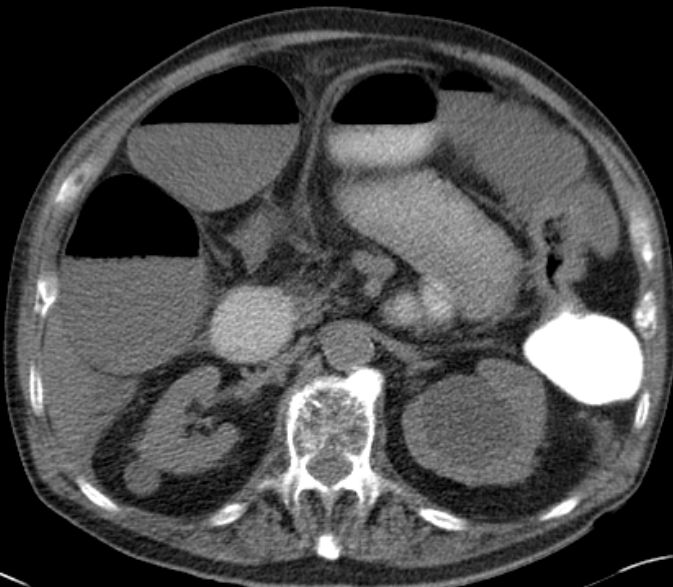

| Klinik | Blut im Stuhl, Verstopfung oder Durchfall, Blähungen, krampfartige Bauchschmerzen. | Stenosierender Tumor der linken Flexur mit Ileus.![]() | |||||||||||||||||